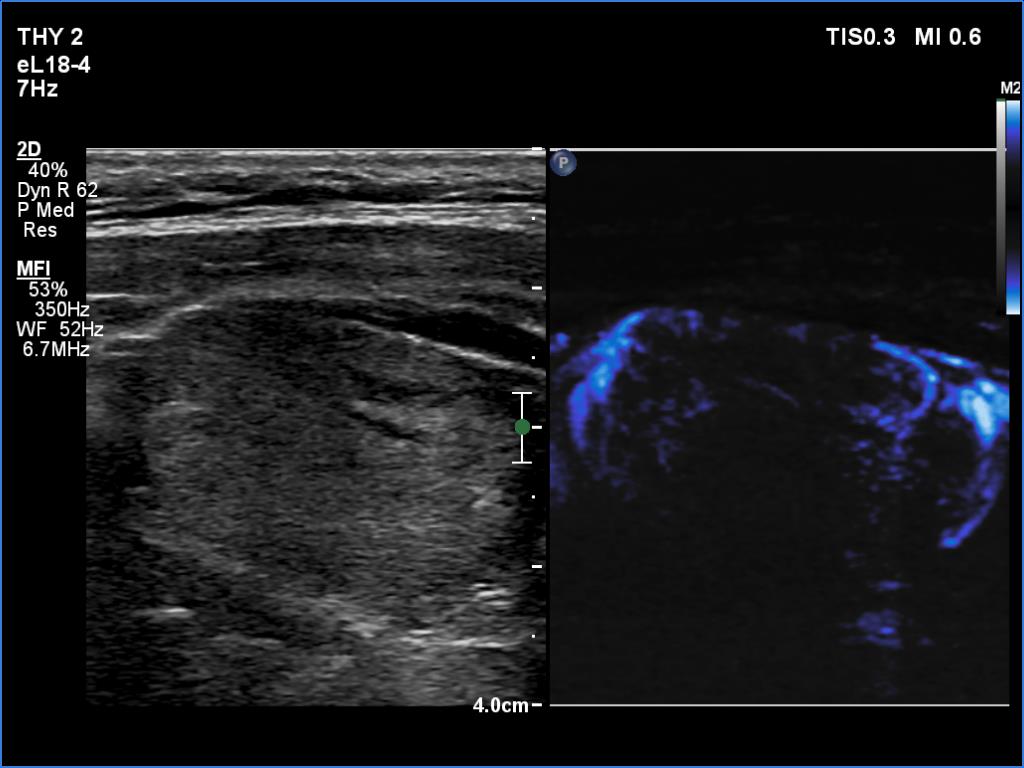

Right lobe, longitudinal scan

Left lobe, longitudinal scan, microflow imaging. The pattern is characterized by the predominance of perinodular vessels.